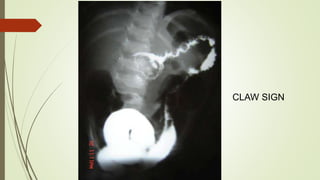

CLAW SIGN

CLINICAL FEATURES  Intermittentpain  Red currant jelly stool  O/E :-  right iliac fossa empty (Dance sign)  Sausage or banana shaped lump with concavity towards umbilicus